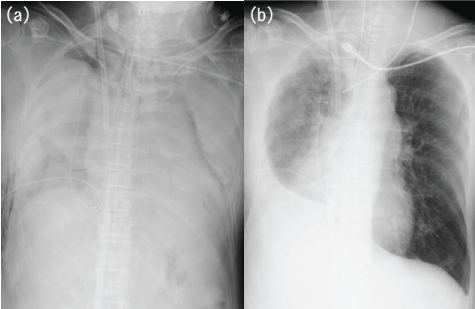

One hour later, ventilation was almost completely interrupted (Figure 1a). VV-ECMO was performed at a flow rate of 3.0-3.5 L/min to maintain oxygen saturation (SaO2) at 80% or more, and results of blood gas analysis showed pH of 7.30, PaO2 of 44 mmHg, PaCO2 of 60 mmHg, lactate of 24 mg/dL and SaO2 of 81% (FIO2of 0.6 or less and peak inspiratory pressure of 25 cm H2O or less). The patient’s condition was stable with blood pressure of 138/84 mmHg and heart rate of 104 beats/min, and transthoracic echocardiography revealed that cardiac output was sufficient. Serum lactate level did not increase and there was no organ failure.

Figure 1: (a) Chest radiography showing almost total airway obstruction; (b) Just before VV-ECMO was discontinued.

On the seventh day of illness, results of blood gas analysis showed pH of 7.43, PaO2 of 150 mmHg, PaCO2 of 45 mmHg, and serum lactate of 11.0 mg/dl (FIO2, 0.45; PEEP, 5 cm H2O; minute volume, 7.9 L/min with no support by VV-ECMO), and VV-ECMO was therefore stopped (Figure 1b).